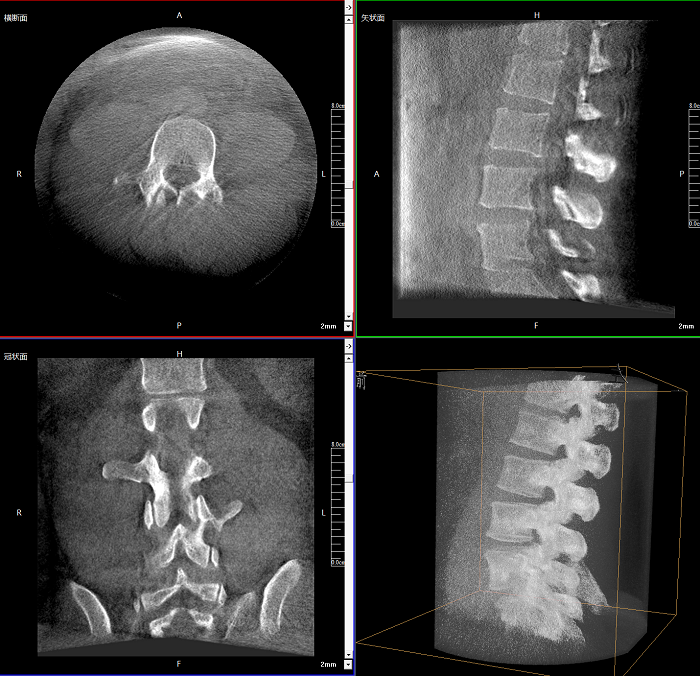

術(shù)中實(shí)時(shí)生成橫斷面、矢狀面、冠狀面及三維影像,可在任意切面、任意角度評估植入物和解剖結(jié)構(gòu)的相對位置。

較9英寸常規(guī)平板視野提升100%,幫助醫(yī)生迅速判斷椎體節(jié)段,定位手術(shù)部位。

400萬像素成像

易于觀察細(xì)微病灶,利于胸部、腹部、脊柱關(guān)節(jié)等復(fù)雜骨骼和軟組織的成像。

Clinical picture

臨床圖片